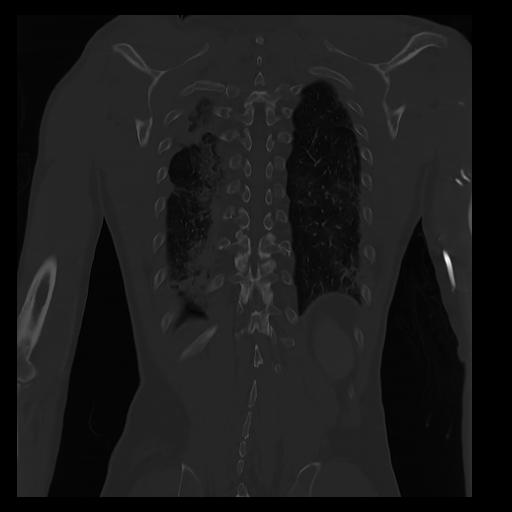

32 PULMON,CE,Coronal,3.000,PULMON,Coronal,